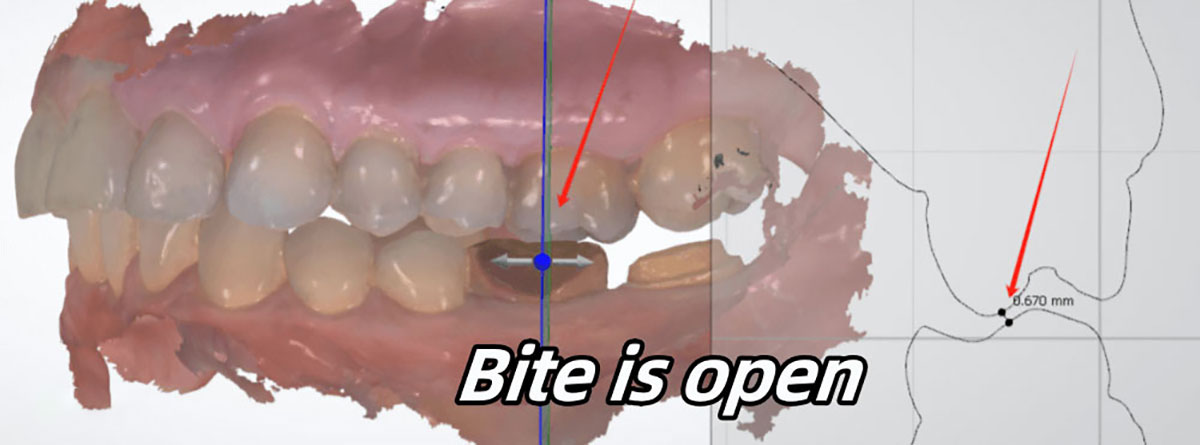

In most cases, however, we cannot find correct bite, or even cannot find any bite relationship. Under those circumstance, we will have to print 3D models, and articulate the upper and lower models by hand.

In this case, the bite is open. Our 3Shape measurement shows that the gap between upper and lower is 0.670 mm. If we make a crown with this bite, doctors will find the crown is with high occlusion.